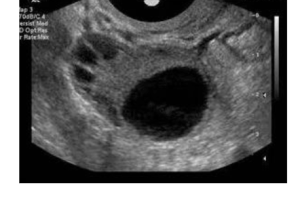

卵泡监测有什么用 卵泡监测是针对女性不孕的一种检查方法,能够通过卵泡检查发现女性不孕的病因,在试管婴儿手术中,卵泡监测技术也被普遍运用,期作用如下: 1、根据卵泡监测报告分析女性是卵泡发育问题还是排卵障碍问题; 2、试管婴儿中卵泡监测的用处主要是为了观察卵泡发育情况,以确定是否促排成功,制定取卵时间…